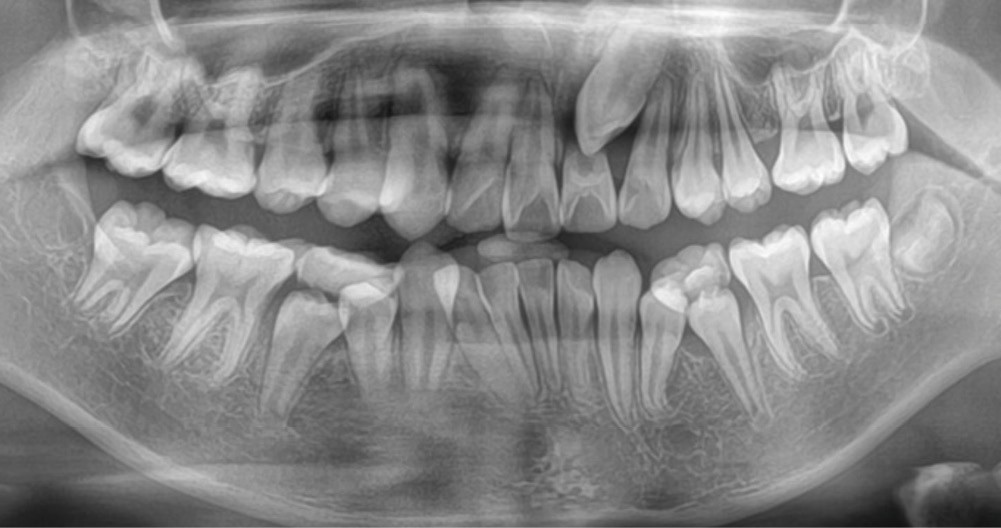

Une patiente âgée de 12 ans se présente en consultation, motivée par la position de son incisive centrale maxillaire, décrite comme « en avant », marquée par une dyschromie et une mobilité de grade 2 selon Muhlemann. L’examen clinique montre l’absence de 23 sur l’arcade, une dysharmonie dents-arcade marquée, un surplomb accentué, et une déviation des milieux inter-incisifs, conséquence du comblement spontané de l’espace de 23. L’ensemble s’inscrit dans un contexte de Classe I d’Angle molaire. L’orthopantomogramme révèle l’inclusion de 23, associée à une résorption radiculaire étendue aux deux tiers de 21. La 22 ne présente aucune altération visible.

La patiente, de profil normodivergent, présente une Classe I squelettique sans troubles fonctionnels (fig. 1-8).

L’objectif du traitement est la correction de la DDA tout en assurant le remplacement de la 21 compromise. Décision a été prise d’extraire 34 et 44, ainsi que 21 et 14. La traction de la 23 a été réalisée à l’aide de forces légères, sur un arc transpalatin (fig. 9). Le nivellement et l’alignement, puis une mécanique par glissement ont permis d’aménager l’espace suffisant à la stratification de la canine. Elle associait un ressort en nickel-titane à des élastiques de Classe II (4 ½ oz, 3/16’’) sur un arc en acier .019×.025. Une phase d’ingression a été réalisée pour ajuster le niveau du bord libre de la canine à celui de l’incisive controlatérale (fig. 10-12).